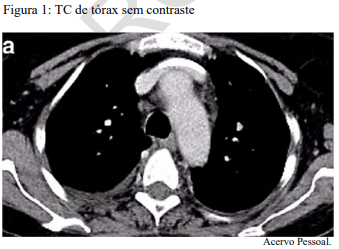

Com base nesse caso clínico, nas imagens apresentadas e nos conhecimentos médicos correlatos, julgue o item a seguir.

O paciente tem indicação, nesse momento, de lobectomia superior direita por VATS, com linfadenectomia mediastinal.

O linfonodo hipercaptante no PET desse paciente, representado na figura 2, trata-se do paratraqueal direito.